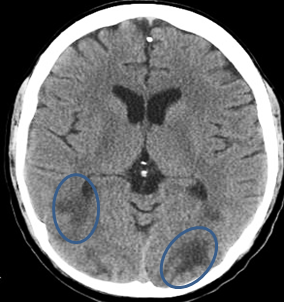

Case Snapshot: Left-Hand Paralysis in a Middle-Aged Male with Prior Infarction

In the accompanying CT image, a male in his 40s with residual left-hand paralysis presents for neuroimaging evaluation. Axial brain CT reveals an irregular low-density area (LDA) in the right frontal lobe, consistent with a prior cortical-subcortical infarct. Such subtle changes, particularly on initial CT, may be challenging to detect, underscoring the necessity of follow-up imaging and MRI when warranted.

Understanding such chronic infarcts is crucial for differentiating them from PRES and other acute conditions.